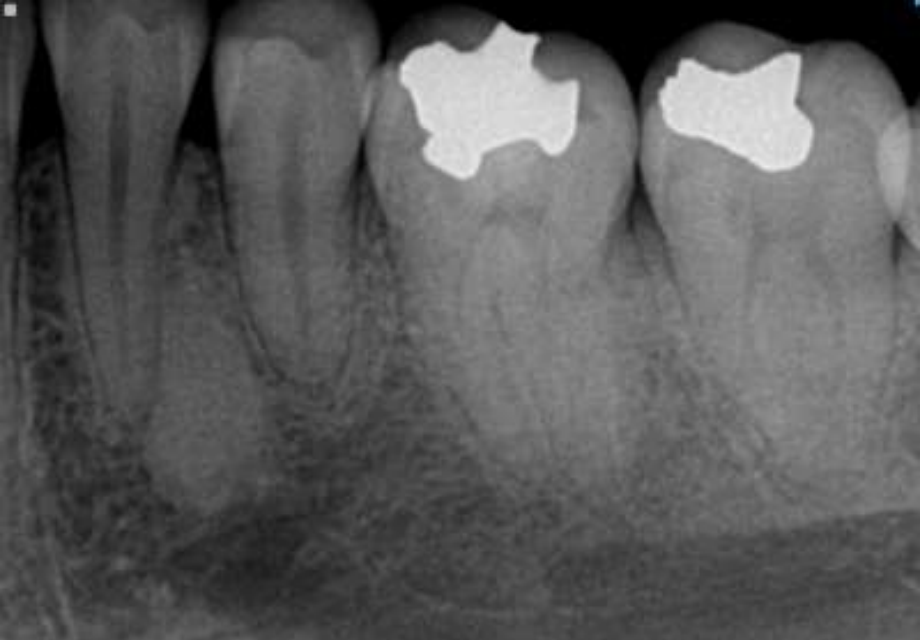

what are radiographic findings of odotomas?

• Well defined, corticated

• Radiolucent band/soft tissue capsule inside the cortical border

• Internal content is largely radiopaque

• Maybe associated with unerupted tooth

COMPOUND odontomas

• Internal content is largely radiopaque- made of multiple tooth like structures called denticles

• Maybe be associated with unerupted tootH